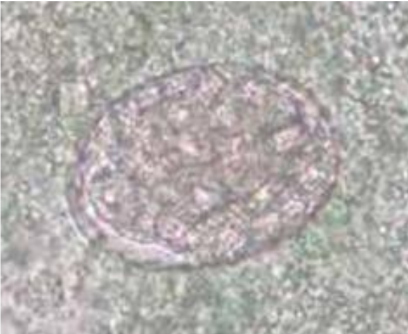

Schistosoma mansoni

Schistosoma japonicum